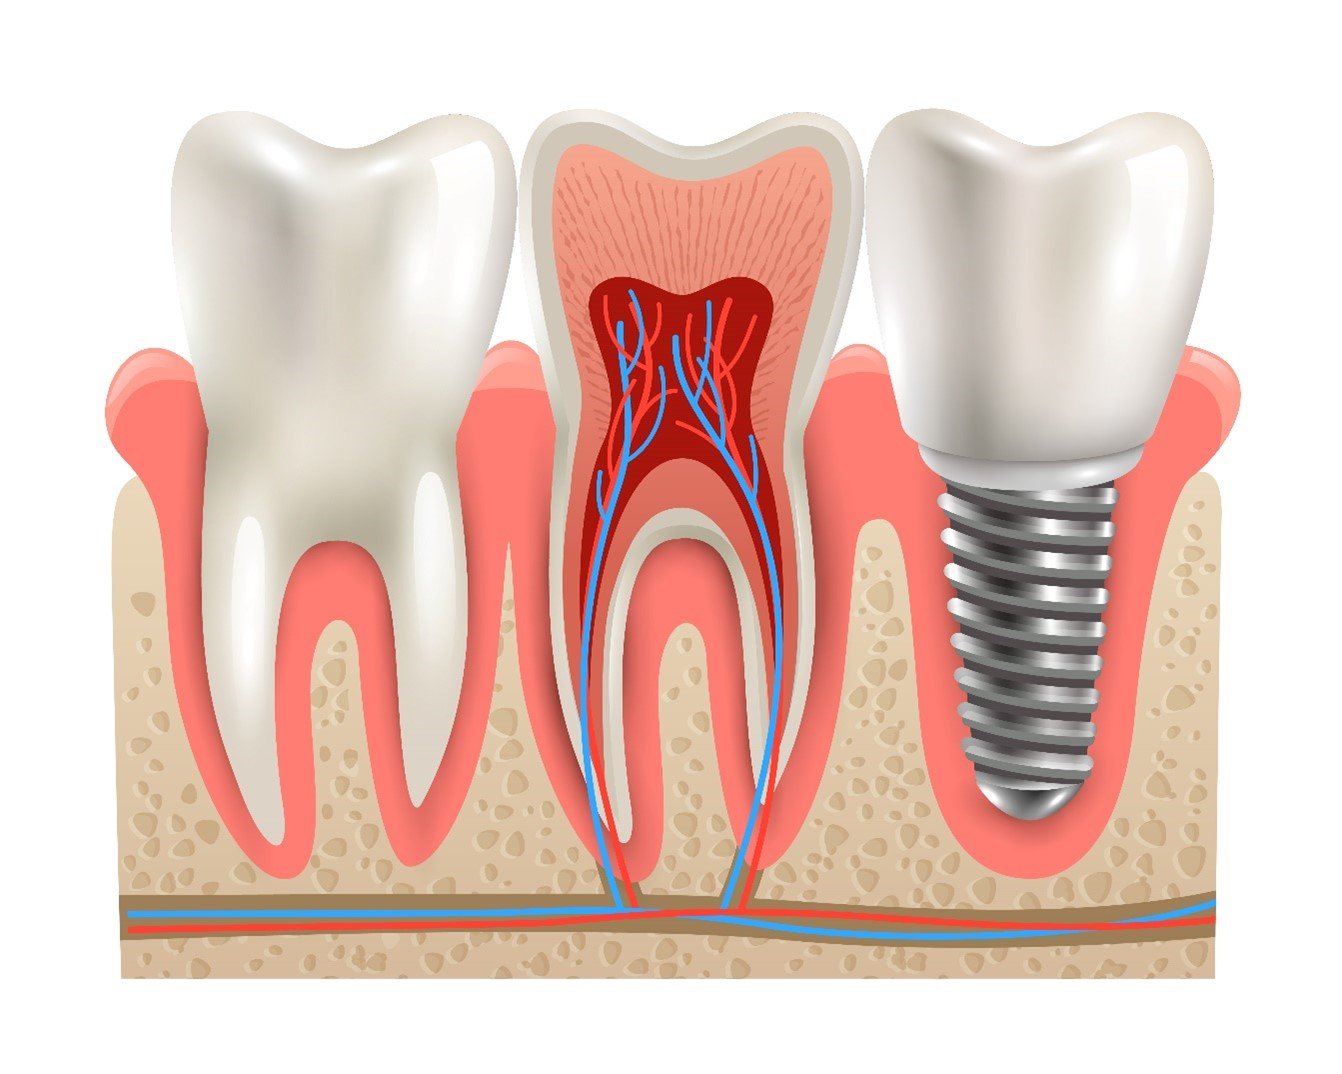

Los implantes dentales de alta gama son dispositivos diseñados para reemplazar dientes ausentes o dañados de manera excepcionalmente eficaz. A diferencia de las prótesis removibles, los implantes dentales se integran de manera permanente en el hueso de la mandíbula, lo que los hace extremadamente estables y funcionales. Están fabricados con materiales de la más alta calidad, como titanio y cerámica, lo que garantiza su durabilidad y resistencia a lo largo del tiempo.

- Preservación del hueso: Los implantes estimulan el hueso de la mandíbula de manera similar a las raíces de los dientes naturales. Esto ayuda a prevenir la pérdida ósea, un problema común cuando se pierden dientes y no se reemplazan.